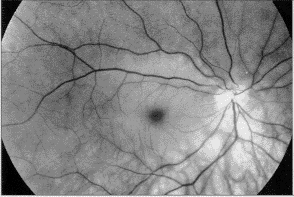

一位49岁的妇女因右眼视力突然丧失转来做进一步诊治。视力丧失发生在做眼科检查的前1天。右眼无光感,根据瞳孔传入障碍、视网膜后极部白色水肿并伴有樱桃红点(图1)这些典型表现诊断为视网膜中央动脉阻塞。双侧眼底检查同时显示了典型的倾斜视盘综合征的特征。荧光血管造影显示动静脉转换时间的明显延迟。球后注射血管扩张剂后视力没有提高。广泛的系统检查无阳性发现。2年后患者经历了1次一过性脑中风,这次的系统检查显示抗核抗体水平增高。得出结论她患有胶原血管病。距初次检查3年后,眼底检查发现在视盘的下部有视乳头前血管环(图2)。荧光血管造影显示在动脉期此环被充盈(图2)。

图1 左,右眼的无赤光图像显示倾斜的视盘和具有一符合樱桃红点的暗斑的视网膜后极部白色水肿。右,荧光血管造影(48秒)显示动静脉转换时间的明显延迟

图2 3年后。左,眼底显示已经在视盘下缘发展的视乳头前血管环(箭头)。注意眼底的下部呈现低色素,这在倾斜视盘综合征中很典型。右,荧光血管造影(30秒)显示动静脉转换时间的持续延迟及此环在动脉期的充盈